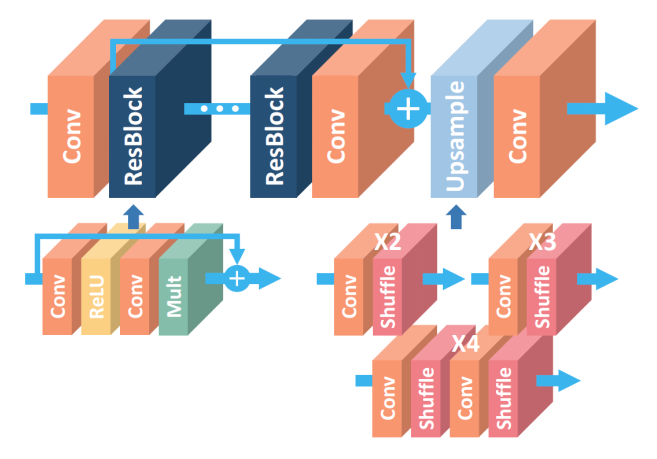

10.3、EDSR

In [25]

from paddle.nn import Layer

from paddle import nn

import math

n_feat = 64

kernel_size = 3

# 残差块 尺寸不变

class _Res_Block(nn.Layer):

def __init__(self):

super(_Res_Block, self).__init__()

self.res_conv = nn.Conv2D(n_feat, n_feat, kernel_size, padding=1)

self.relu = nn.ReLU()

def forward(self, x):

y = self.relu(self.res_conv(x))

y = self.res_conv(y)

y *= 0.1

# 残差加入

y = paddle.add(y, x)

return y

class EDSR(nn.Layer):

def __init__(self):

super(EDSR, self).__init__()

in_ch = 1

num_blocks = 32

self.conv1 = nn.Conv2D(in_ch, n_feat, kernel_size, padding=1)

# 扩大

self.conv_up = nn.Conv2D(n_feat, n_feat * 4, kernel_size, padding=1)

self.conv_out = nn.Conv2D(n_feat, in_ch, kernel_size, padding=1)

self.body = self.make_layer(_Res_Block, num_blocks)

# 上采样

self.upsample = nn.Sequential(self.conv_up, nn.PixelShuffle(2))

# 32个残差块

def make_layer(self, block, layers):

res_block = []

for _ in range(layers):

res_block.append(block())

return nn.Sequential(*res_block)

def forward(self, x):

out = self.conv1(x)

out = self.body(out)

out = self.upsample(out)

out = self.conv_out(out)

return out10.4、SRResNet